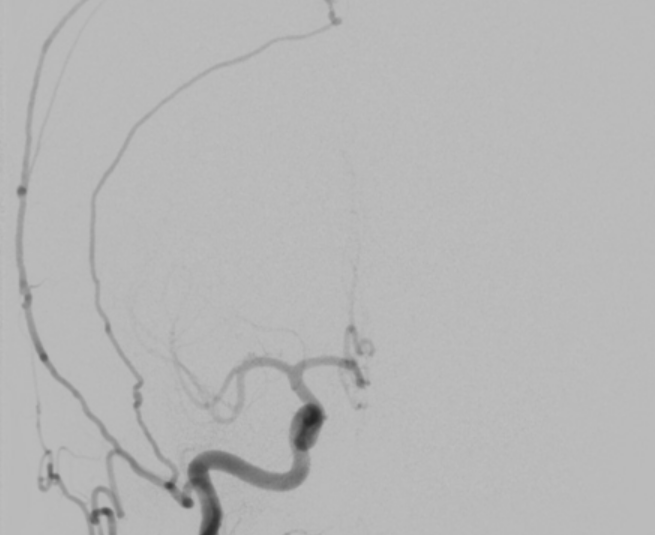

While a CT (computed tomography) or MRI (magnetic resonance imaging) test of either the brain or spinal cord will typically first detect these lesions, catheter-based diagnostic (cerebral or spinal) angiography is essential to fully understand and characterize the dAVF. This evaluation allows your doctor to determine your future risk of symptoms and your treatment options. Treatment of a dAVF depends on whether symptoms are present or not, how large the lesion is, where it is located, and a host of other features only determined by the diagnostic (cerebral or spinal) angiogram.

Historically an adjunctive treatment, Embolization can now be a primary therapy for select lesions. During embolization we pass a catheter through the groin up into the arteries in the brain that lead to the DAVF, and inject a material into these arteries that blocks off the artery and reduces the blood flow through the DAVF.